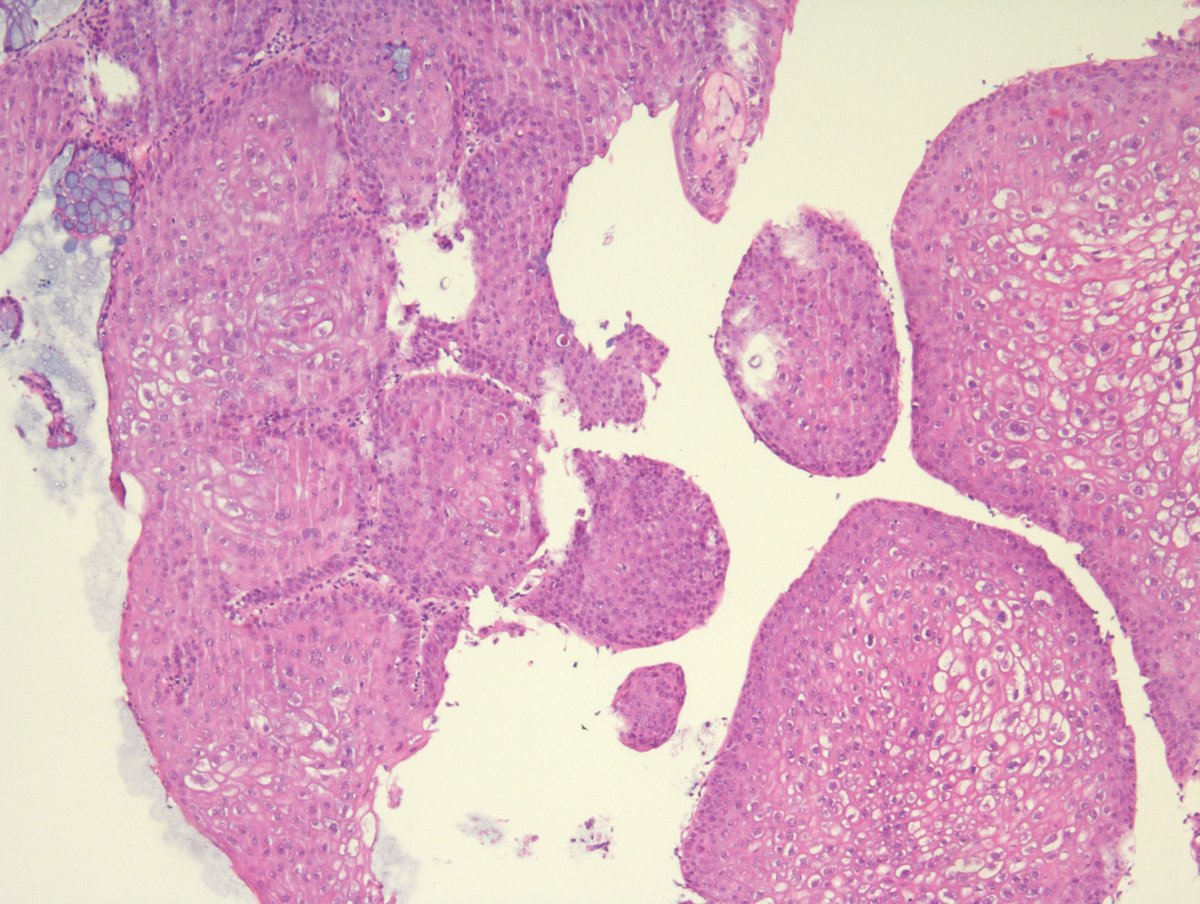

Intratubular seminoma and intratubular embryonal carcinoma in the same field (From a radical orchidectomy specimen for mixed germ cell tumour) #PathTwitter #Pathology #PathResidents #GUPath

DrLaurenceGalea's tweet image. Intratubular seminoma and intratubular embryonal carcinoma in the same field

(From a radical orchidectomy specimen for mixed germ cell tumour)

#PathTwitter #Pathology #PathResidents #GUPath